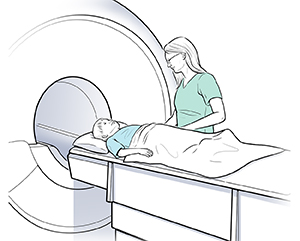

Your Child's Heart MRI or CT Scan

During the scan

|

| A cardiac MRI scan takes pictures of your child’s heart. |

The scan is done by a technologist. It is interpreted by either a radiologist or a cardiologist. A radiologist is a healthcare provider trained to diagnose and treat problems with imaging technology. A cardiologist is a healthcare provider trained to diagnose and treat heart problems. The scan can take place in either a hospital or outpatient imaging center. A cardiac MRI scan lasts about 60 to 90 minutes. A cardiac CT scan lasts about 30 minutes. Here is what you can generally expect during the scan:

Your child lies on a table that slides into the scanner.